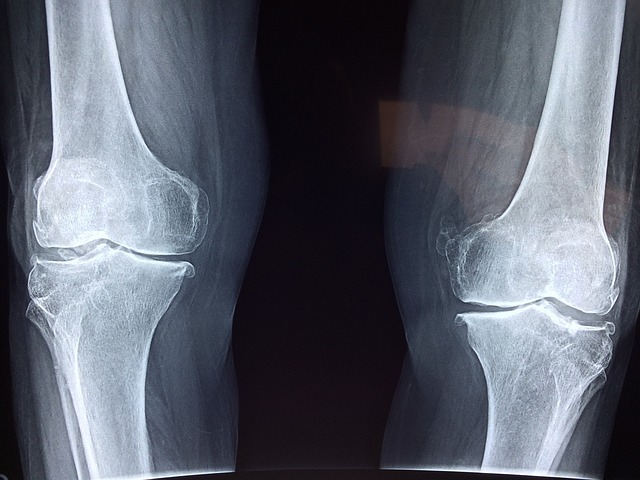

- 이모튼 캡슐은 1997년 발매된 일반의약품으로, 골관절염과 치주질환에 의한 출혈 및 통증 치료에 사용됩니다.

- 현재 이모튼 캡슐은 골관절염, 치주질환에 의한 출혈과 통증의 보조 요법으로 허가받은 일반의약품입니다. 향후 효능·효과가 '성인 무릎 골관절염의 증상 완화'로 확대될 예정입니다.